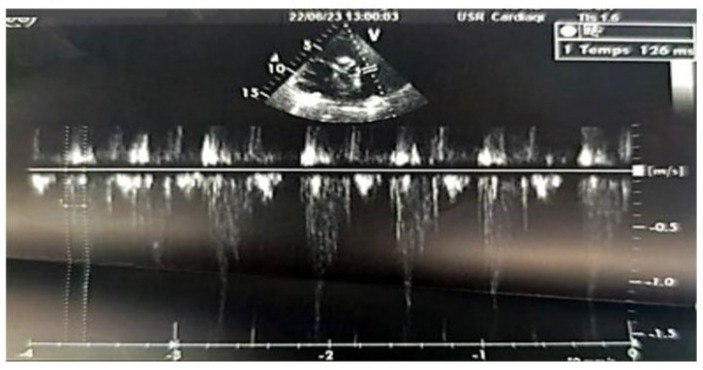

We report the case of a 70-year-old female patient with a history of poorly controlled arterial hypertension, presenting with two coexisting conditions that required either a two-step approach or simultaneous management, involving a thyroidectomy followed by cardiac surgery under cardiopulmonary bypass (CPB). In our case, a simultaneous approach was chosen following a multidisciplinary consultation. With a medical history of poorly controlled arterial hypertension, a multinodular plunging goiter in hyperthyroidism treated with carbimazole 10 mg/day, and atrial fibrillation associated to severe aortic valve stenosis managed with acenocoumarin 4 mg (¼ tablet/day) and bisoprolol 2.5 mg/day, the patient presented with a progressively worsening condition. The onset of her symptom’s dates back to five months prior, marked by a brief episode of syncope, prompting an emergency consultation. Initial evaluation revealed tachycardia due to atrial fibrillation on a background of severe aortic valve stenosis. She was placed on symptomatic treatment. The course of her illness was characterized by a worsening baseline dyspnea, progressing from NYHA class II to class III, accompanied by exertional palpitations without chest pain. The patient was referred to the ENT consultation for progressively worsening dyspnea, associated with orthopnea and a massive goiter, and cardiology consultation for the evaluation of her heart disease. During her recent assessment she also reported reduced exercise tolerance and occasional dizziness with neck symptoms, including subclavicular pain and swallowing limitations. Clinical examination revealed a large goiter deforming the neck, visible on inspection, with signs of tracheal compression. Cardiac auscultation identified an intense systolic ejection murmur at the aortic focus radiating to the carotids, with no signs of right-sided heart failure or peripheral edema. Thyroid ultrasound showed a multinodular goiter containing hypoechoic cystic areas and calcifications, with a plunging thoracic component compressing cervical and superior mediastinal structures. A cervical-thoracic CT scan, with and without contrast injection, confirmed the plunging nature of the goiter. It extended into the anterior mediastinum, displacing the trachea and major vessels without evidence of invasion. The scan revealed a multinodular goiter characterized by generalized thyroid gland enlargement, predominantly affecting the left lobe, with an irregular, lobulated contour. The goiter is characterized by heterogeneity, macrocalcifications, and uneven enhancement, marking hypodense necrotic and/or cystic fluid-filled areas. The large goiter measures 12.13 x 9.06 x 6.63 cm in the left lobe, 10.5 x 6 x 5.36 cm in the right lobe, and 5 cm in the isthmus. It extends upwards to the submandibular spaces and laterally towards the anterior and posterior spinal spaces, particularly on the left side. The jugulo-carotid vascular axes are displaced laterally and posteriorly, but remain unobstructed. The goiter extends downward into the superior level of the anterior mediastinum, filling the prevascular space and pushing vascular structures posteriorly. It reaches the level of the superior border of the aortic arch, coming into contact with the supra-aortic trunks, exerting a mass effect, but without invasion or obstruction. The upper aerodigestive pathways are unobstructed and symmetrical, although there is posterior and rightward displacement at the larynx and trachea level, without narrowing or impact on their lumen, which remains patent and of normal size. (Figure 1) Transthoracic echocardiography revealed severe degenerative aortic stenosis with high pulmonary arterial hypertension for age (PASP through tricuspid regurgitation at 55 mmHg). The left ventricle was non-dilated, hypertrophied with an indexed mass of 107.11 g/m² (eccentric remodeling), end-diastolic diameter (EDD) at 44 mm, end-systolic diameter (ESD) at 28 mm, and preserved systolic function with an ejection fraction (EF) of 55% (biplane Simpson method). (Figure 2)

Figure 9: 2D echocardiographic image in the parasternal short-axis view, with pulsed Doppler pointed a few millimeters below the pulmonary valve (in the right ventricle), showing a pulmonary acceleration time to reach the peak velocity with an intermediate value of 126 ms, which is neither short (<90 ms) nor long (>130 ms).